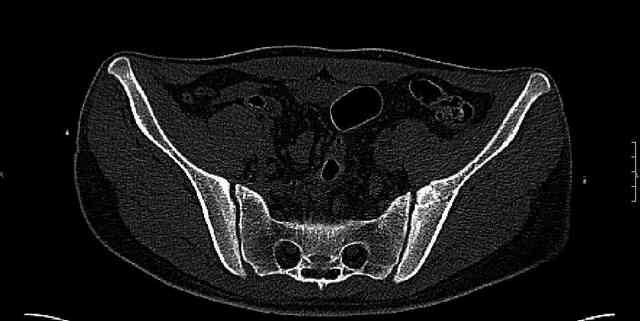

Some more images. Does it help to guess which part of the acetabulum is displaced?

Normal appearing SI joints and a healed posterior column limb... my bet's on caudal segment displacement.